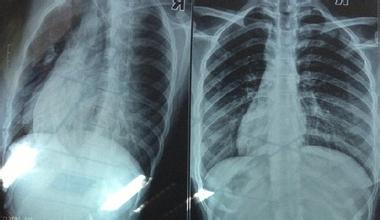

我院治療多根多處肋骨骨折新進(jìn)展

多根多處肋骨骨折常由巨大暴力所致,胸廓外形發(fā)生改變,以胸部疼痛、呼吸困難為主要表現(xiàn),常合并有肺挫裂傷、血?dú)庑氐?,局部活?dòng)胸壁可隨呼吸出現(xiàn)矛盾運(yùn)動(dòng),約占肋骨骨折的5%,可危及生命。早期,疼痛以及胸廓穩(wěn)定性受破壞,可使呼吸動(dòng)度受限、呼吸淺快和肺泡通氣減少,病人不敢咳嗽,痰潴留,從而引起下呼吸道分泌物梗阻、肺不張或感染,呼吸衰竭,這在老弱病人或原有肺部疾患的病人尤應(yīng)予以重視。后期,肋骨畸形愈合,造成肋間神經(jīng)長期受壓,患者長期受到肋間神經(jīng)痛的困擾,嚴(yán)重影響生活質(zhì)量,治療效果欠佳,胸廓畸形,肺容量縮小,肺活量部分喪失,影響工作生活。所以,手術(shù)治療進(jìn)行干預(yù),在多根多處肋骨骨折的治療中顯得尤為重要。

通過對(duì)病人的術(shù)后隨訪,復(fù)查肋骨對(duì)位好,雙側(cè)胸廓對(duì)稱,胸壁無塌陷,呼吸良好,疼痛明顯減輕,無1例傷口感染,患者基本恢復(fù)正常,行胸部CT及相關(guān)核磁共振檢查均不受影響,全組無一例有排異不適等需取出者。